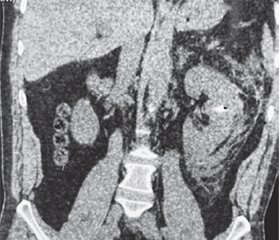

Версия для печати

Актуальність. У військовий час поранення нирки є комбінованим із травмами інших органів. Стандартом лікування таких поранень є негайна ревізія з подальшою органозберігаючою операцією, але на сьогодні не вироблені чіткі критерії відбору таких поранених до хірургічного лікування, не вивчені морфологічні та функціональні зміни в нирках внаслідок вогнепального поранення. Мета: демонстрація можливостей мініінвазивних технологій при ізольованому вогнепальному осколковому проникному пораненні живота з ушкодженням нирки та наявністю стороннього тіла (металевого осколка) нирки. Матеріали та методи. Два військових отримали поранення внаслідок артилерійського обстрілу в серпні 2023 року. Доставлені до передової хірургічної групи через 1 та 3 доби після поранення, виконано обстеження за FAST-протоколом, перев’язку. Через 6 годин були доставлені до Військово-медичного клінічного центру Східного регіону. Результати. Поранений П., 48 років, надійшов через 3 доби після поранення. Загальний стан пацієнта стабільний, лабораторні показники в нормі. При огляді виявлено вхідний отвір в поперековій ділянці справа, діаметром 20 мм, без ознак кровотечі. За даними МСКТ виявлено металевий осколок верхнього полюса правої нирки 12 × 7 мм. Тяжкість поранення нирки класифіковано як Grade 2 згідно з класифікацією American Association for Surgery and Trauma. Виконано лапароскопічне видалення металевого осколка правої нирки. Осколок був видалений з паренхіми нирки за допомогою інструмента магнітного для ендовідеоскопічної діагностики та видалення металевих феромагнітних сторонніх тіл. Час операції становив 95 хвилин. Пацієнта виписано на 4-ту добу. Поранений С., 45 років, надійшов через 1 добу після поранення. Загальний стан пацієнта стабільний. Лабораторно виявлено анемію легкого ступеня. При огляді виявлено вхідний отвір у лівій поперековій ділянці діаметром 15 мм. За даними нативної МСКТ діагностовано металевий осколок середнього сегмента лівої нирки 8 × 8 мм з гематомою заочеревинного простору 111 × 30 × 68 мм. Тяжкість поранення нирки класифіковано як Grade 3. Виконано лапароскопічне видалення металевого осколка лівої нирки, дренування гематоми заочеревинного простору. Осколок видалено після дренування заочеревинної гематоми та незначного розширення вхідного вогнепального отвору нирки за допомогою інструмента магнітного для ендовідеоскопічної діагностики та видалення металевих феромагнітних сторонніх тіл. Час операції становив 125 хвилин. Пацієнта виписано на 6-ту добу. Висновки. Лапароскопічний доступ може застосовуватись для видалення металевих осколків при ізольованому вогнепальному ушкодженні нирки. Для забезпечення ефективності та малоінвазивності рекомендовано застосування сучасного хірургічного магнітного інструмента. Виконання подібних оперативних втручань можливо за наявності оснащення, навченого персоналу та може бути відтерміновано.

Background. In wartime, kidney injuries are combined with damage to other organs. The standard of care for these injuries is immediate revision with subsequent organ-preserving surgery. But as of today, clear criteria for selecting such wounded people for surgical treatment have not been developed, renal morphological and functional changes due to gunshot wounds have not been studied. The aim is to demonstrate the possibilities of minimally invasive technologies in an isolated gunshot shrapnel penetrating abdominal wound with renal trauma and the presence of a foreign body (metal fragment) in the kidney. Materials and methods. Two soldiers were injured as a result of artillery shelling in August 2023. They were taken to the frontline surgical team 1 and 3 days after the injury, where they were examined according to the FAST protocol and bandaged. After 6 hours, they were taken to the Military Medical Clinical Center of the Eastern Region. Results. Wounded P., 48 years old, was admitted 3 days after the trauma. The patient’s general condition is stable, laboratory values are normal. The examination revealed an entrance wound in the lumbar region on the right, 20 mm in diame-ter, without signs of bleeding. According to multislice computed tomography, 12 × 7 mm metal fragment of the superior pole of the right kidney was detected. The severity of renal trauma was classified as grade 2 according to the American Association for the Surgery of Trauma classification. The fragment was removed from the kidney parenchyma using a magnetic instrument for endovideoscopic diagnosis and removal of metal ferromagnetic foreign bodies. The surgery duration was 95 minutes. The patient was discharged on day 4. Wounded S., 45 years old, was admitted one day after the injury. The patient’s general condition is stable. Laboratory tests showed mild anemia. Examination revealed an entrance wound in the left lumbar region with a diameter of 15 mm. According to the native multislice computed tomography, a metal fragment in the middle segment of the left kidney of 8 × 8 mm with a retroperitoneal hematoma of 111 × 30 × 68 mm was diagnosed. The severity of the kidney trauma was classified as grade 3. Laparoscopic removal of the metal fragment of the left kidney and drainage of the retroperitoneal hematoma were performed. The fragment was removed after drainage of the retroperitoneal hematoma and slight dilation of the entrance gunshot wound of the kidney using a magnetic instrument for endovideoscopic diagnosis and removal of metal ferromagnetic foreign bodies. The surgery lasted 125 minutes. The patient was discharged on day 6. Conclusions. Laparoscopic access can be used to remove metal fragments from isolated gunshot wounds of the kidney. The use of a modern surgical magnetic instrument is recommended for a minimally invasive approach and to ensure efficiency. Such surgical interventions are possible with the availability of equipment, trained personnel and can be postponed.